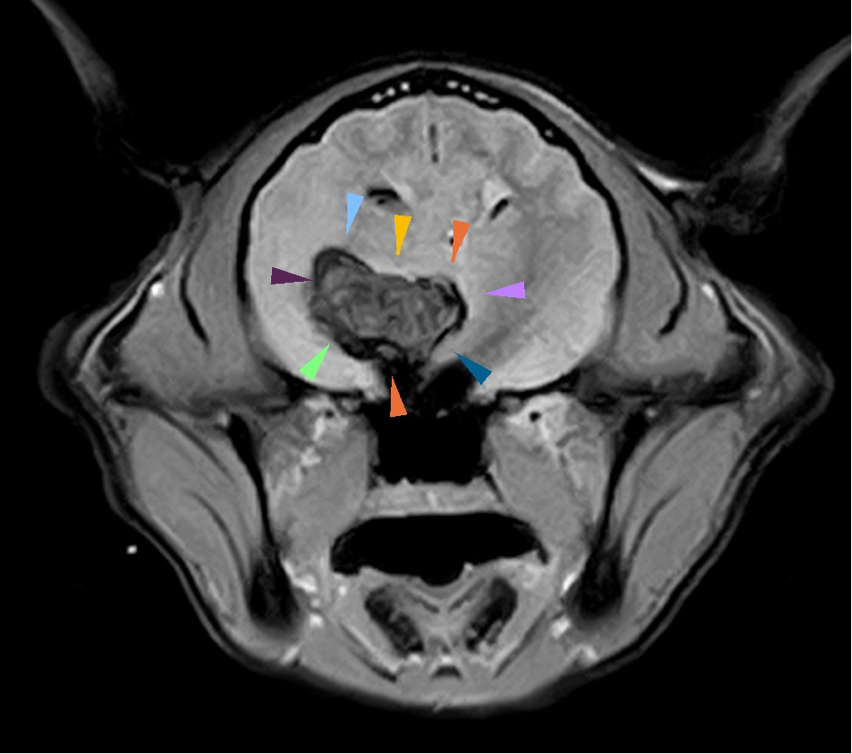

MRIでは視床と呼ばれる脳の領域に巨大な血腫を生じていました(画像の矢印で囲まれた部分)。本来、この大きさの血腫は手術で取り除くことが望ましいのですが、できた場所が悪く手術できない部分でした。血腫のため、自然と吸収され小さくなることが予測されたため、点滴と脳を保護する薬で治療を継続しました。

MRI画像。T2*強調画像と呼ばれる特殊な撮影で血腫や出血の診断をします。